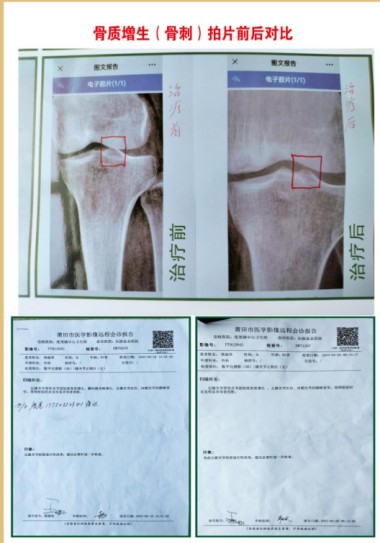

①病历依据,2012年一2016年,53岁,女,腰椎左侧弯L4,LS1。椎间隙狭窄,L3,L4,L5,LS1椎间盘向周围膨出,双侧椎间孔稍狭窄,L4,L5椎间盘积气并向周围膨出,L3,L4,L5,LS1不同程度骨质增生,走路身体变形,怕动手术风险,五年时间治疗无效,外用药水热敷配合手法操作自己治疗,22天治愈。